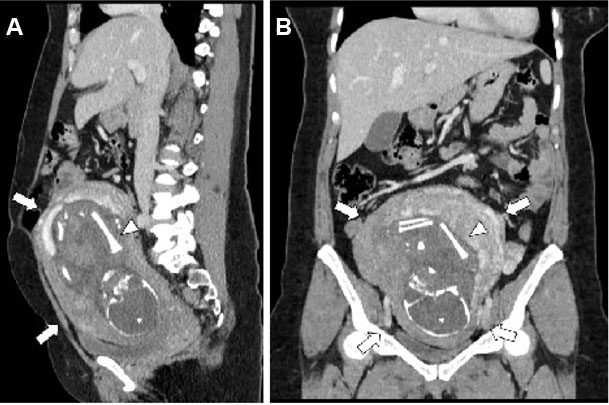

Our patient is a 38-year-old woman from Burundi with no significant past medical history. She had two full-term pregnancies. Her contraception (injection) was efficient until June 2023. During the evaluation of a breast mass, she was diagnosed with grade 3 invasive ductal carcinoma of the right breast (T1c, N1, M0, according to the AJCC 8th edition classification) which was both hormone receptor-positive (HR+) and Human Epidermal Growth Factor Receptor 2 positive (HER2+) (Figure 1).

After one month, we made a staging computed tomography (CT) scan for a palpable pelvic mass, which incidentally revealed a pregnancy on April 3, 2024. The patient was referred to a prenatal diagnostic unit, where gestational age was estimated at 25 weeks and 4 days, with an estimated due date of July 13, 2024.

Figure 1: 38 year-old woman with clinically palpable abdominal mass during neoadjuvant treatment for breast cancer Contrast-enhanced portal venous abdominal CT—multiplanar sagittal (A) and coronal reconstruction (B) showed an unexpected gravid uterus (arrows) with one foetus who had ossified head (*), spine and femurs (arrowheads) compatible with a 5–6 months pregnancy. Calculated foetal doses by our physician were 7.04 mGy (no risk of congenital malformation).